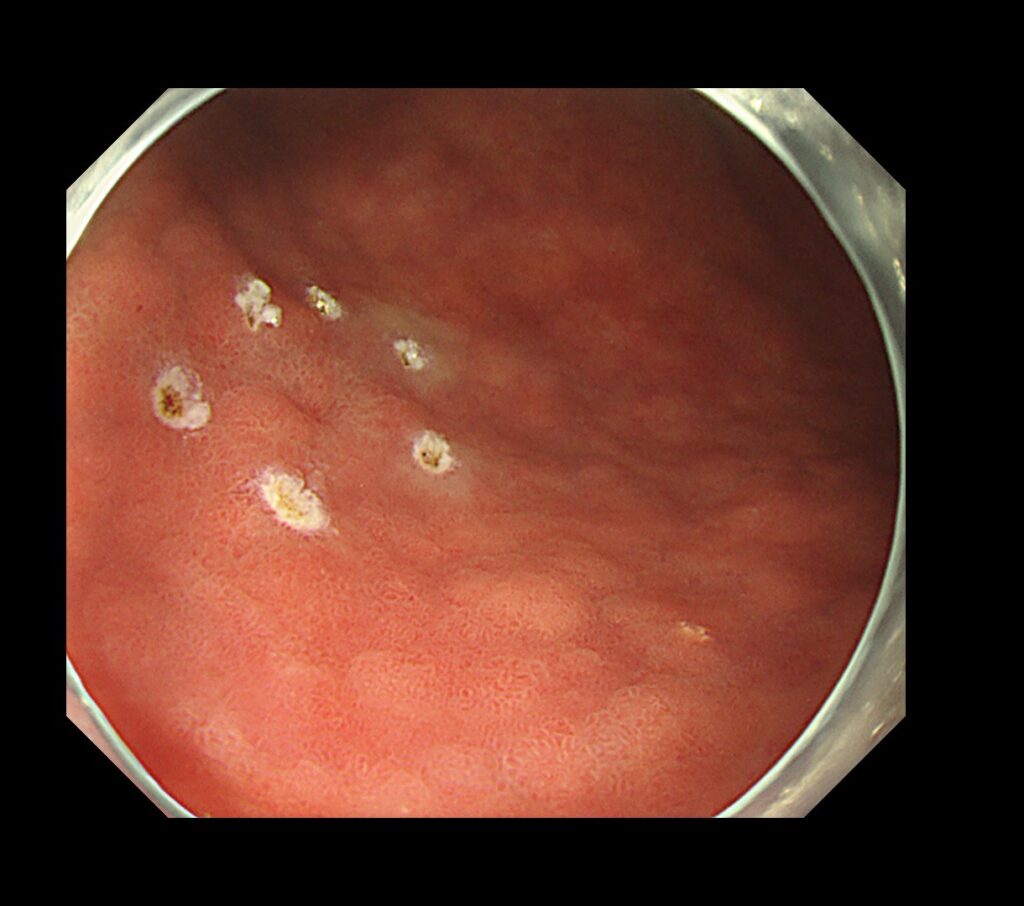

TXIモード(色と凹凸を強調するモード)に変えるとようやく、隠れていた胃癌が視認できるようになります。

今回の病変は、NBIモードより、上述したTXIモードのほうが癌の視認がしやすい病変です。